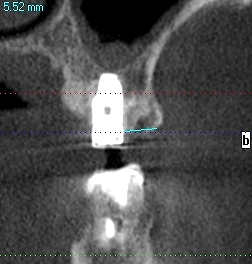

上顎洞への解剖距離が大切です

上顎洞を破ると別の問題が出ます

上顎洞を持ち上げたりします

頬側が骨幅が取れるケースと取れないケースもあります